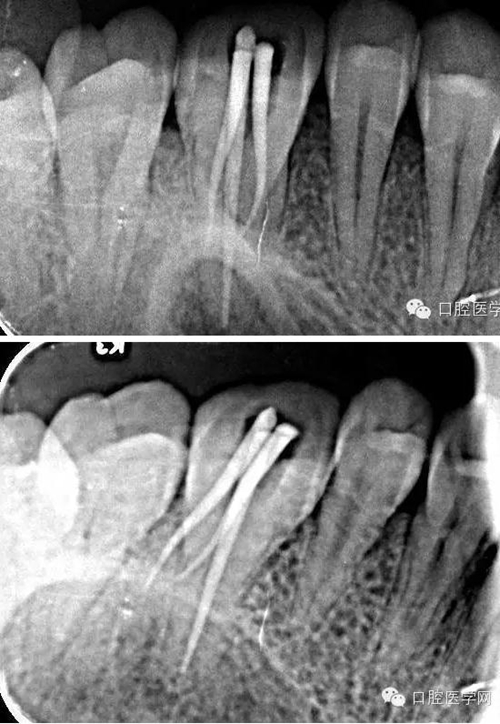

復(fù)診:原暫封材料在位,患牙無不適癥狀。去除原暫封材料,大量沖洗液沖洗根管,紙尖干燥根管,試尖合適,AH-plus糊劑+登士柏大錐度牙膠充填,光固化樹脂充填。拍術(shù)后片顯示充填良好,建議一周后全冠修復(fù),術(shù)后拆除牙齦縫合線,局部消毒。

術(shù)中試尖x線片:

術(shù)后x線片: